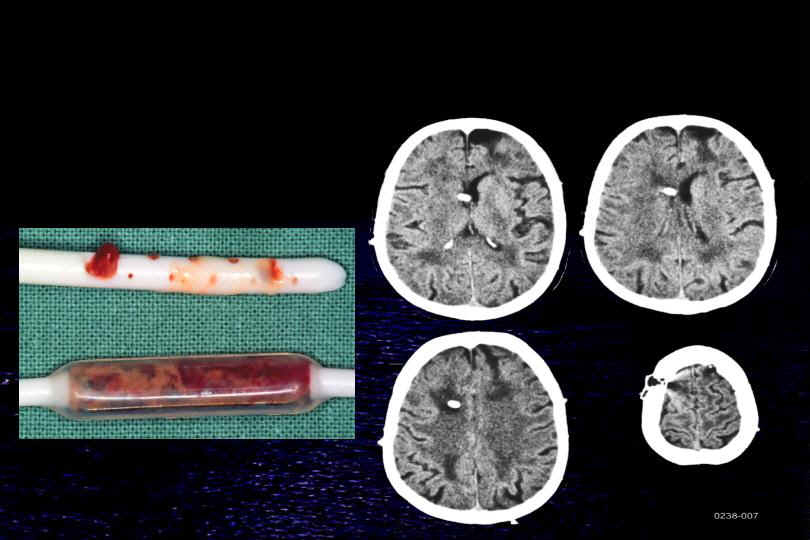

wie unter 4. Slit ventricle Syndrom erwähnt, kann es im Rahmen einer chronischen Überdrainage zum Verstopfen des Ventrikelkatheters kommen. Das Bild unten zeigt eine solche Komplikation. Unschwer erkennt man auf dem CT (rechts) die schlitzförmigen Ventrikel und dass der Ventrikelkatheter praktisch vollständig von Hirngewebe umschlossen ist. Die Folge ist auf dem linken Bild deutlich zu sehen. Die Löcher des Katheters und auch weitere Anteile des Shunts sind mit Gewebe verstopft. Dieser Shunt kann nicht mehr funktionieren.